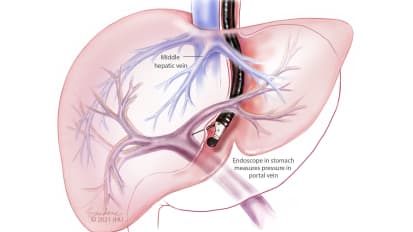

Endoscopic Ultrasound Measures Pressure in Hepatic Portal Vein

Gaining access to the liver through the stomach, Olaya Brewer Gutierrez and her therapeutic endoscopy colleagues at Johns Hopkins use endoscopic ultrasound to obtain a direct reading of the pressure in the hepatic portal vein.